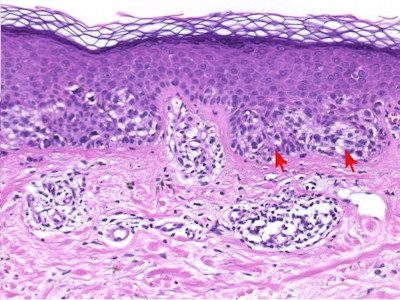

Histologische

variantenDe naevi naevocellularis worden ingedeeld in 3 histologische

varianten

-

junctional naevus (naevus naevocellularis

marginalis): opeenhoping van naevuscellen in de epidermis

dermal

/

intradermal naevus (naevus naevocellularis dermalis):

opeenhoping van naevuscellen in de dermis

compound naevus

(naevus naevocellularis epidermo-dermalis): opeenhoping van naevuscellen in

zowel dermis als epidermis

Zie ook de ingescande PA-coupes (

compound

naevus) van de

afdeling

pathologie van de University of Toronto.